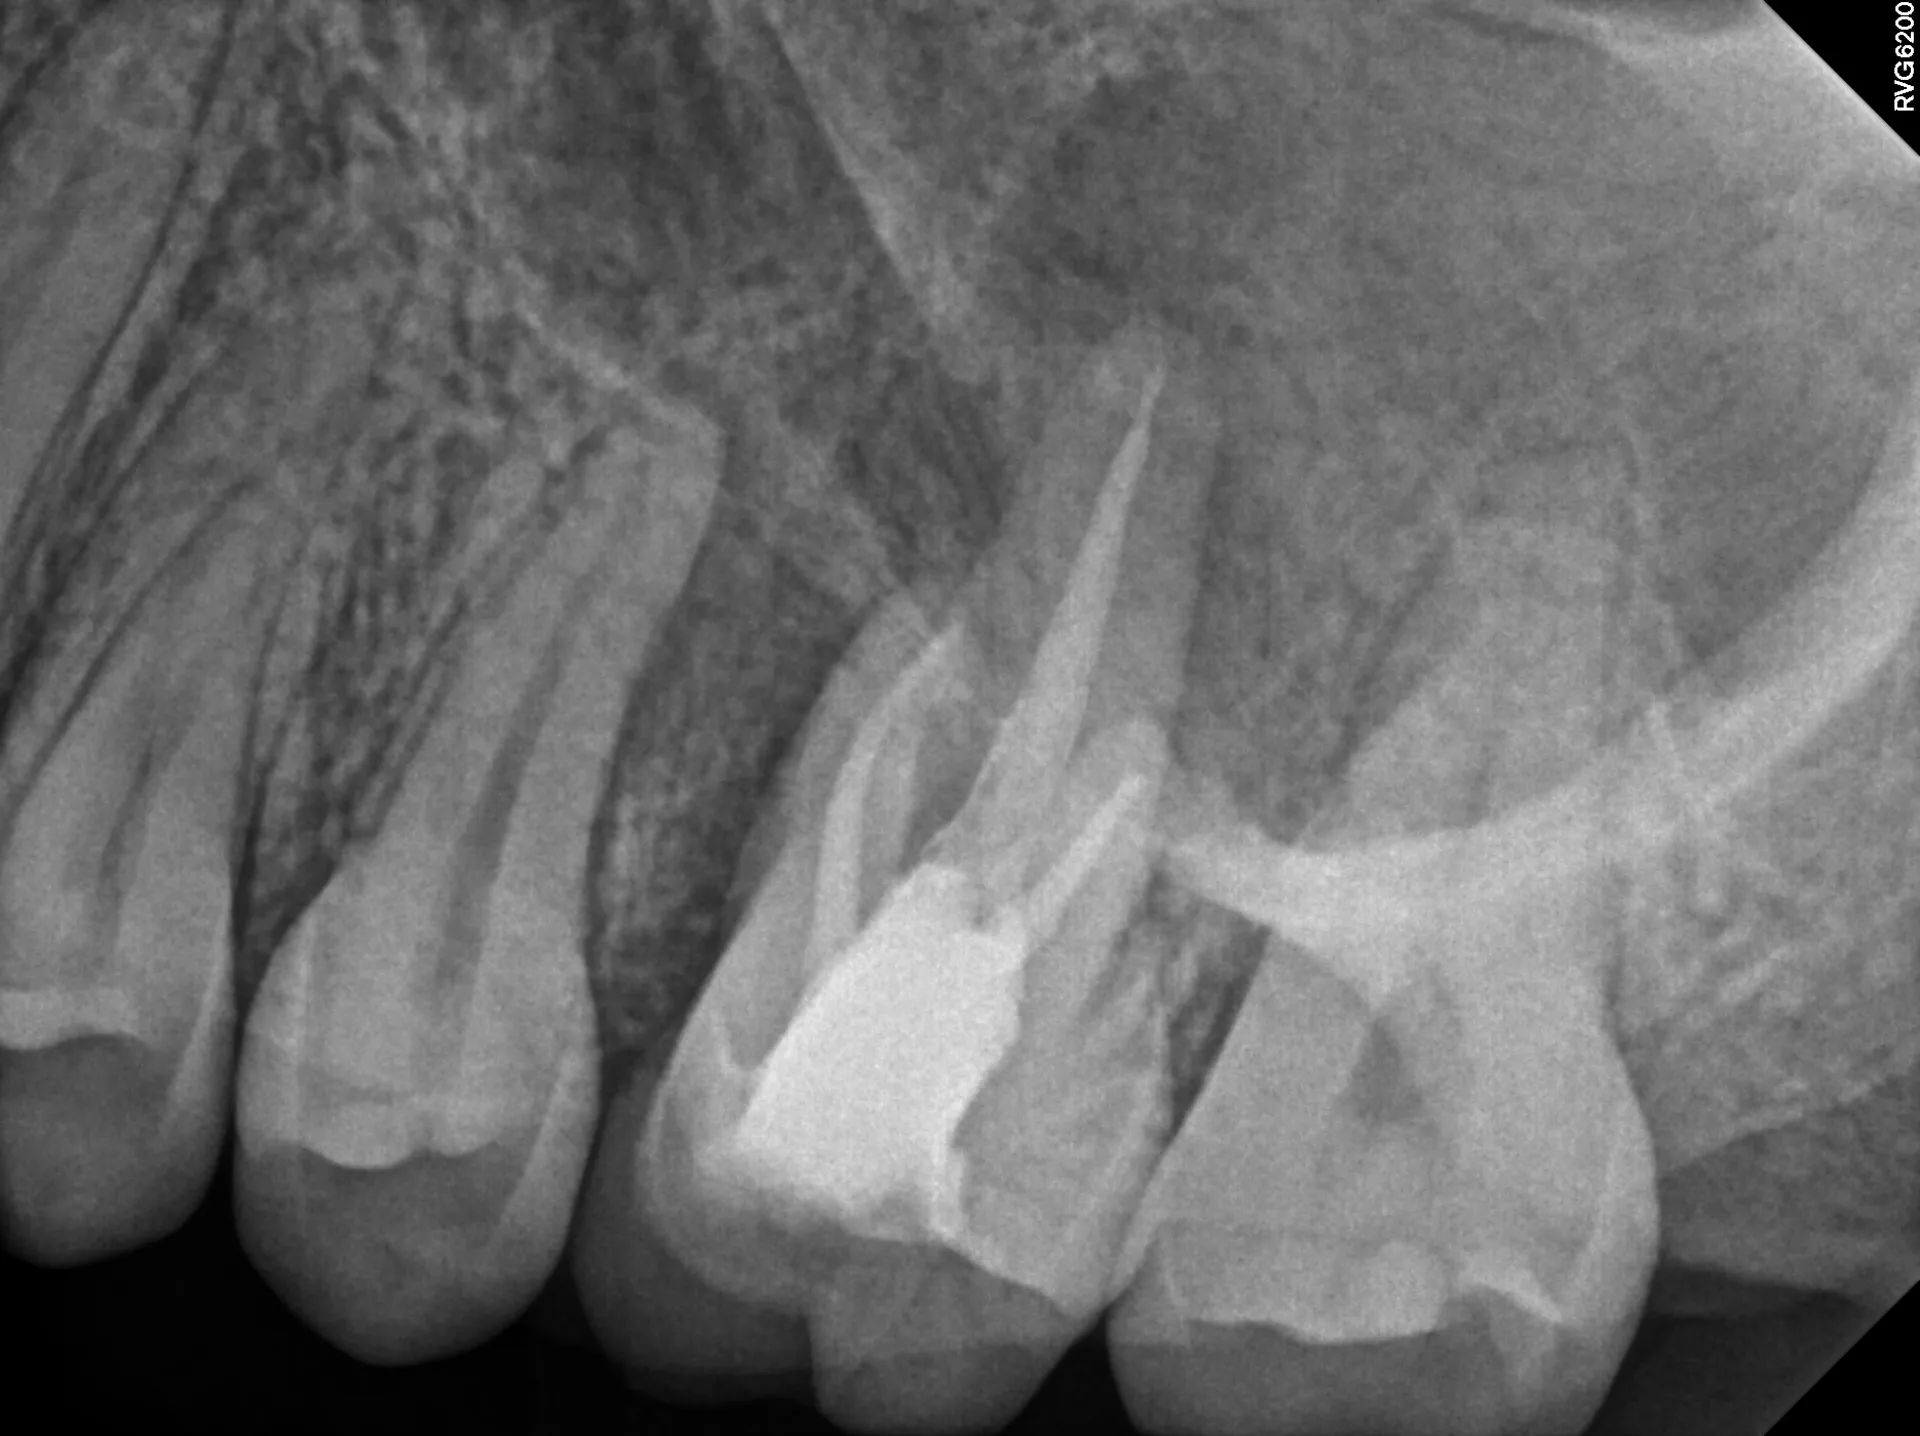

Combined endo-perio lesions represent one of the most challenging diagnostic and treatment scenarios in dentistry. The patient presented with a 9mm pocket on the distal of tooth #14, purulent exudate, and a large periapical radiolucency. Two questions needed answering: (1) Is this primarily an endodontic problem with secondary periodontal involvement, or vice versa? (2) What's the appropriate treatment sequence?

The diagnostic key was recognizing that the pocket communicated directly with the apex—classic for an endo-perio lesion originating from pulpal necrosis. Necrotic pulp tissue drains through the periodontal ligament, creating a pathway that mimics periodontal disease but has an endodontic origin.